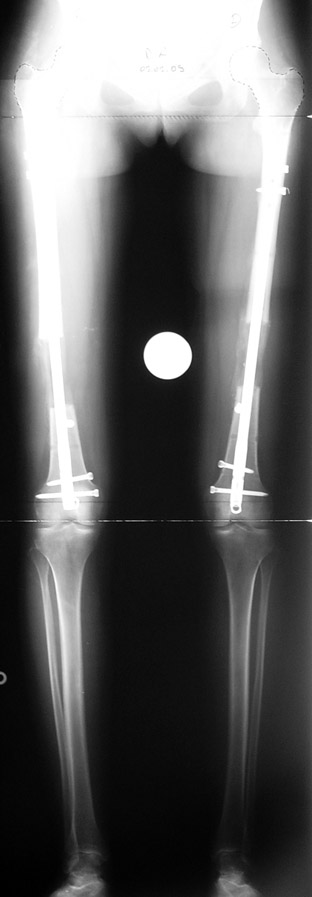

Postoperatif Bakım: Distraksiyona (Kemik parçalarının arasının birbirinden uzaklaştırılması yöntemi) 10. günde başlanır. Günde 4 defa 6 saatte bir 0.25mm uzatma yapılır. Operasyondan 1-2 gün sonra kalça ve diz çevresi hareketlere başlanır. Alt ekstremite kısalıklarının tedavisi uzun yıllar boyunca hem hasta hem de cerrah için zorluklarla dolu olmuştur. İlizarov’un distraksiyon osteogenezisi kavramını tanımlamasından sonra geliştirilen teknikler bu konuda yeni bir çağın öncüleri olmuşlar ve daha önceki yıllarda görülen komplikasyonların oldukça azaldığı uygulamalar olarak anılmışlardır.

Günümüzde ekstremite uzatma uygulamaları için tercih edilecek yöntemde aranan en önemli özellikler şöyle sıralanabilir; uygulama süresi, “alignment” (kemiğin anatomik ve mekanik aksı) sağlama , toplam ameliyat sayısı, rejeneratın refraktürden korunabilmesi, çivi dibi infeksiyonu ve sebep olabileceği komplikasyonların asgari miktarda tutulması, hareket açıklığının korunması, “iyileşme zamanı “, günlük hayattaki konfor ve uygulama maliyeti.

Biz son zamanlarda, seçilmiş vakalarda, uzatma sonrası uzunluğu ve “alignment’ı” korumak amacı ile unilateral dinamik aksiyel fiksatör ve kilitli intramedüller çivi kombinasyonunu tercih etmekteyiz. Bu yöntemin ön şartları medullanın en dar çapının 7 mm.’den geniş olması ve uzatma sonrası distalde en az 8 cm. uzunluğunda çivi kalabilmesidir. İntramedüller çivi hem uzatma esnasında femurun üzerine gelen makaslama ve bükülme kuvvetlerini nötralize etmekte hem eksternal fiksasyon süresini kısaltmakta, hem de yeni oluşan kemiği kırıklara karşı korumaktadır. Serimizde bir vakada subtrokanterik femoral osteotomi yapılmıştır. İntramedüller çiviye rağmen varus angulasyonu oluşması yönünde bir dezavantaj tespit etmedik.

İntramedüller çivi ve eksternal dinamik aksiyel fiksatör kombinasyonu teknik olarak standart İlizarov uygulamalarından daha zordur. Ancak şu avantajlar yöntemi cazip hale getirmektedir; eksternal fiksasyon süresinde kısalma, refraktüre karşı korunma, erken rehabilitasyon, azami hareket genişliği kazanma ve günlük yaşam konforu. Bu avantajlar artan maliyet , artan kan kaybı ve potansiyel derin infeksiyon gibi dezavantajların önüne geçmektedir. Sonuç olarak, bulgularımızın eşliğinde, intramedüller çivi üzerinden femoral uzatma tekniğinin güvenilir ve dayanıklı bir metod olduğunu ve bizce standart İlizarov uygulamalarına üstünlük sağlayan avantajlar getirdiğini söyleyebiliriz.